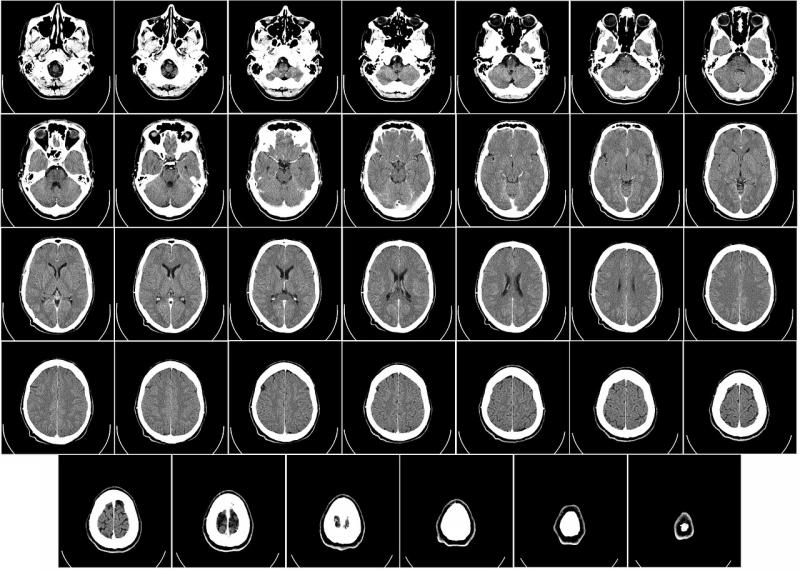

vRAD, also known as Virtual Radiologic (an affiliate of MEDNAX), is grooming the currently experimental algorithm as a traffic cop for its picture archiving and communication system (PACS) workflow. The algorithm, which has been taught to recognize the signs of intracranial bleeding in CT brain scans, is being trained to direct suspicious images to vRAD’s neuroradiologists.

Recognizing this condition is a high priority in emergency medicine and, consequently, at vRAD, which interprets medical images for thousands of ERs across the U.S. On average, the results of emergency computed tomography (CT) of patients with intracranial bleeds are distributed, read and interpreted by vRAD neuroradiologists in 10 to 15 minutes.

Shannon Werb, vRAD chief information officer, explains that the algorithm, working with vRAD’s PACS, is being developed to channel the images to neuroradiologists licensed to practice in the state where the patient was scanned. The first of these neuroradiologists to become available would immediately open the study. This could cut the time elapsed from exam to interpretation from the current 10 to 15 minutes to 5 or 10 minutes, Werb said.